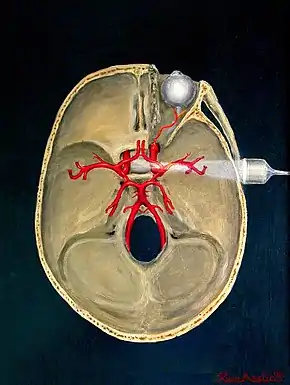

Transcranial Doppler insonation of the cerebral circulation

Transcranial Doppler (TCD) and transcranial colour Doppler (TCCD) measure the velocity of blood flow through the brain's blood vessels transcranially (through the cranium). These modes of medical imaging conduct a spectral analysis of the acoustic signals they receive and can therefore be classified as methods of active acoustocerebrography. They are used as tests to help diagnose emboli, stenosis, vasospasm from a subarachnoid hemorrhage (bleeding from a ruptured aneurysm), and other problems. These relatively quick and inexpensive tests are growing in popularity. The tests are effective for detecting sickle cell disease, ischemic cerebrovascular disease, subarachnoid hemorrhage, arteriovenous malformations, and cerebral circulatory arrest. The tests are possibly useful for perioperative monitoring and meningeal infection.[7] The equipment used for these tests is becoming increasingly portable, making it possible for a clinician to travel to a hospital, to a doctor's office, or to a nursing home for both inpatient and outpatient studies. The tests are often used in conjunction with other tests such as MRI, MRA, carotid duplex ultrasound and CT scans. The tests are also used for research in cognitive neuroscience.